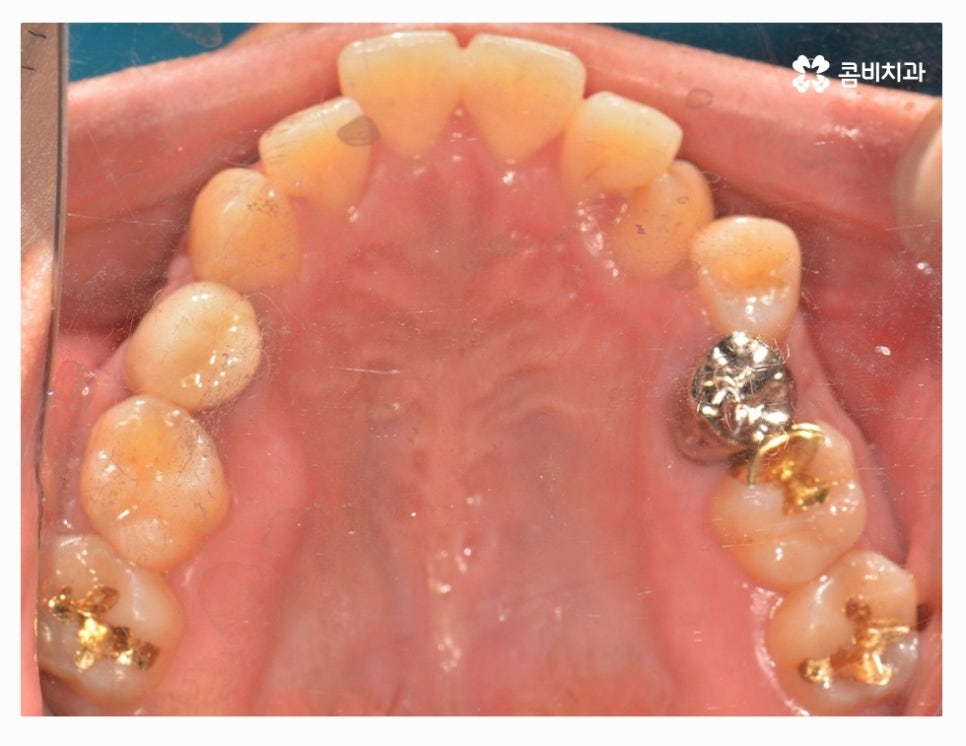

오늘 소개드릴 환자분은 윗니와 아랫니가 제대로 맞물리지 않는

부정교합 사례이며 클리피씨교정을 통해서 치료가 진행된 사례라고 할 수 있어요.

부정교합 환자분들의 경우 발치나 수술이 필요한 경우가 있는데

치아교정을 진행할 때 치아의 이동 공간을 고려해야 하므로

치간 삭제나 어금니 후방 이동으로도 치아 이동 공간이 부족하다면

발치를 필수적으로 해야 하는 경우가 있어요.

클리피씨교정은 세라믹 재질이기 때문에 심미적으로도 우수한 편이며

브라켓과 와이어 고정을 위한 철사를 사용하지 않기 때문에 철사로 인해 찔리거나

입안이 뜯겨 피가 나는 경우를 예방할 수 있는데요.